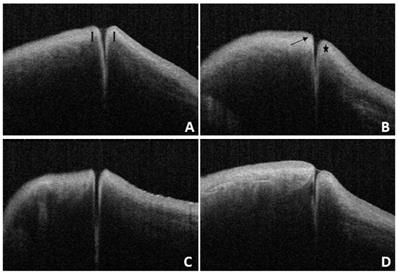

Figure 6

A and B: OCT images of the same subjest with the eyes open (A) and closed (B).

Int J Med Sci Image

The characteristic presence of dense fibrous tissue in continuity with the tarsal plate in and around the punctum was histologically demonstrated by Kakizaki et al [14]. Timlin et al. found that OCT imaging of the palpebral margin tissue of the nasal and temporal punctum showed three layers and speculated that the highly reflective layer observed on OCT corresponded to dense fibrous tissue [6]. Scanning electron microscopy of the normal lacrimal canaliculus found multiple collagen fibers attached to the muscle bundles of the orbicularis oculi on the outer surface of the distal lacrimal canaliculus, indicating that this muscle might play a potential role in tear drainage [15]. The orbicularis oculi muscle and lacrimal sacs can be compressed and relaxed through blinking to form a pump-like mechanism that drains tears into the nasal cavity [16-18]. When the eyes are closed, the punctum and orbicularis oculi muscle around the lacrimal canaliculus contract, causing the punctum to shrink and move inward. Meanwhile, the lacrimal canaliculus shortens and is compressed, together with the lacrimal sac, enabling tears to flow from the nasolacrimal duct into the nasal cavity. When the eyes are open, the punctum and orbicularis oculi muscle around the lacrimal canaliculus dilate, causing the punctum to reopen, and the lacrimal canaliculus and lacrimal sac to expand and extend. Meanwhile, the vertical canaliculus dilates to form an ampulla, enabling tears to enter the lacrimal canaliculus and lacrimal sac by siphoning. In this study, 28 patients (56 eyes) underwent examinations with their eyes open and closed. When the eyes were closed, ELP, ILP, and VCL were smaller than when the eyes were open, and the differences were statistically significant (p<0.05; Table 3 and Fig. 7). The results of this study are consistent with the theory of the lacrimal pump, providing a certain degree of objective imaging basis for the mechanism of the lacrimal pump.

Figure 7

There were statistically significant differences between ELP, ILP, and VCL when the eyes were open or closed.